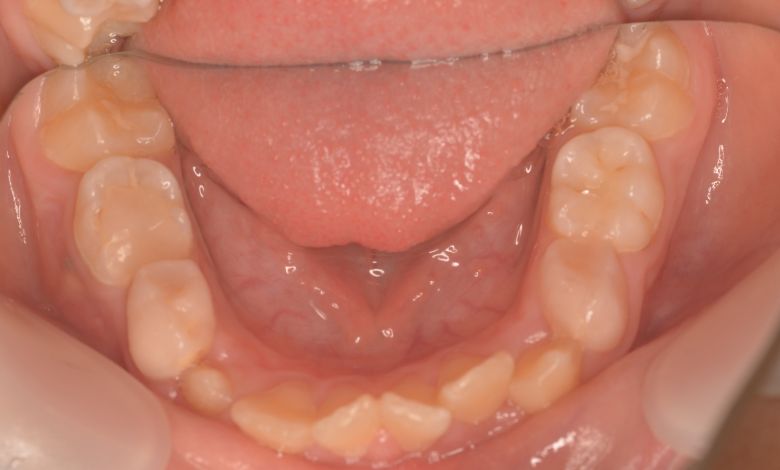

下の前歯が3本、強く重なり合って生えており、歯並びの乱れが目立つ

下顎の歯列では、前歯部に強い重なりが見られ、中切歯および側切歯がねじれたり前後にずれて生えているのが確認できる

前歯部では3歯が大きく重なり、ねじれや傾斜も伴っている。歯列弓は狭く、U字型から逸脱した非対称な形態